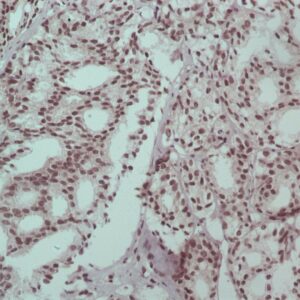

BioGenex offers fluorescein-labeled oligonucleotide probes to detect DNA or RNA using In situ Hybridization (ISH). These probes allow quantitative detection of specific DNA/RNA sequences in their native form within the cells of formalin-fixed paraffin-embedded (FFPE) tissue sections. These probes offer reliable, highly sensitive, and easy-to-perform DNA and RNA ISH assays when used with the BioGenex ISH Detection Systems.